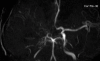

A 31-year-old man presented with dull headache and memory disturbance lasting for one week. Computed tomographic scans revealed acute hydrocephalus. The cerebrospinal fluid contained 53 leukocytes/mm(3), with a mononuclear preponderance and no erythrocytes. Magnetic resonance imaging revealed hydrocephalus and leptomeningeal enhancement. Magnetic resonance angiography and digital subtraction angiography showed supraclinoid occlusion of the right internal carotid artery, which resembled unilateral moyamoya disease. Neuroendoscopic biopsy of a lesion in the septum pellucidum revealed noncaseating granulomas, which was consistent with sarcoidosis. The patient was successfully managed with intravenous methylprednisolone and ventriculoperitoneal shunting. To our knowledge, this is the first case of moyamoya-like vasculopathy associated with neurosarcoidosis.